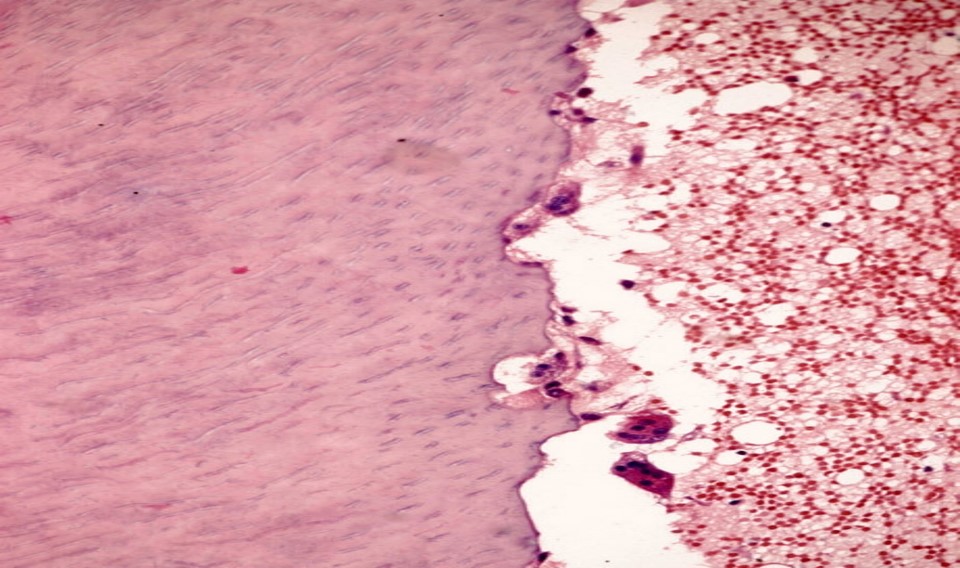

2)病理变化

a.牙根表面出现蚕食状吸收陷窝;

b.处于活动期的可见破骨细胞(图8.3-2);处于静止期的,无破骨细胞,陷窝可被新形成的牙骨质修复。

图8.3-2 牙外吸收